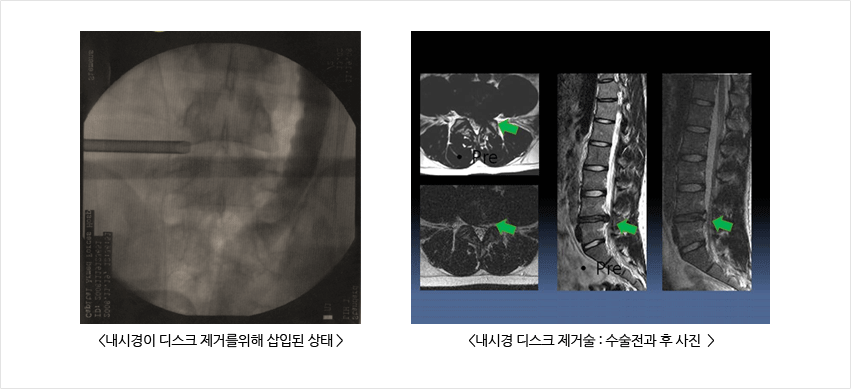

허리디스크 치료 두 번째는 외과적 치료입니다.

몇 가지 수술적 치료법이 있습니다. 복부 절개를 제거하기 위해 신경을 누르는 리본을 제거하는 수술이 있습니다. 허리를 잡은 상태에서 척추를 떼어내는 척추융합술도 있습니다. 마지막으로 레이저로 디스크를 제거하는 레이저 절제술이 있습니다.